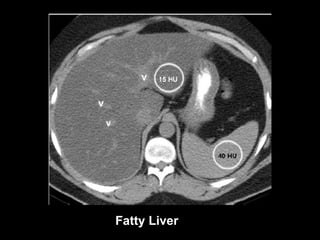

Diagnosis at CT Normal Liver The normal liver has slightly greater attenuation than the spleen and blood. Intrahepatic vessels are visible as hypoattenuated structures Fatty liver Unenhanced CT Attenuation of the liver is at least 10 HU less than that of the spleen or attenuation of fatty liver is less than 40 HU In severe cases, intrahepatic vessels may appear hyperattenuated relative to fat-containing liver tissue.

Normal Liver Fatty Liver At enhanced CT, the comparison of liver and spleen attenuation value is not reliable. Fatty liver can be diagnosed at contrast-enhanced CT if absolute attenuation is less than 40 HU,  but this threshold has limited sensitivity .